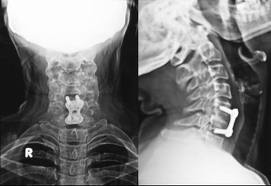

I was overjoyed when Dr. Smith validated my pain as he pointed it out to me when he looked at my MRI. “I see your problem right here!” pointing at three vertebrae that were squished together. The pain was real, not in my head; just imagined! I smiled with satisfaction when I heard his comment, “My gosh girl, you’re a mess!” His next words were even more welcome when he said to me, “I can give you a measure of relief from all the pain you’ve been experiencing through a surgical procedure called ACDF.” He didn’t promise me the sun, the moon and the stars, but he did promise me he could relieve my pain. That was music to my ears.

What is ACDF? It’s an acronym for Anterior Cervical Discectomy and Fusion. I’ll leave the “technical” explanation for your doctor to explain. There are many “variations” of the procedure, enhancing your chances for a complete and successful recovery. (different conditions need different applications to address specific issues unique to your own body or condition.) The ACDF is a procedure where the surgeon goes into the spinal column at your neck through the front, either one side or the other of the voice box and the esophagus. The surgery is actually performed this way so the surgeon can best locate and isolate the involved vertebrae with less damage to connective tissue and tendons making motion possible in the first place. This leads to a quicker healing process. It is said that a successful ACDF procedure can give the pain sufferer immediate relief from all the excruciating symptoms right after surgery. THAT is a very accurate statement!

It’s been my understanding from a patient perspective, there are certain mitigating conditions that directly affect a successful outcome of the ACDF surgery. One of the biggest issues is if the patient is a smoker due to circulation problems. Healing comes slowly, or in some cases, not at all, when people are smokers. Some other factors may be heart conditions or diabetes. In some rare instances, outside conditions can create an environment where the bone grafts may not “take.” In that case, it would be within the doctors’ judgment to make that determination and appropriate action. It was scary for me as the days and weeks passed and my healing was so slow due to the added stress on my body from having an additional surgery so close to my ACDF. I literally felt like the fusion was not taking properly or not at all. When Dr. Smith looked at my follow-up x-rays and said with almost a smile in his voice, “Your procedure is completely fused, it looks really well and I’m very pleased with what I see.” Whew!” I was beginning to think the things I felt in my neck and shoulders were still going to be a part of my everyday life. Ah, not so! I just needed to strengthen them, and his visit gave me a renewed sense of purpose for my exercising.